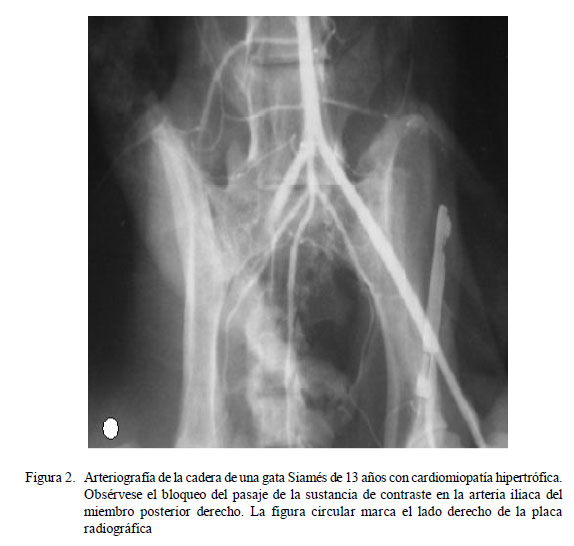

Al examen radiológico contrastado (arteriografía) se evidenció el pasaje del medio de contraste hasta la bifurcación de la aorta, encontrándose obstruido el pase hacia la arteria iliaca del miembro posterior derecho, mientras que pasó con normalidad por todo el paquete vascular del miembro posterior izquierdo (Figura 2).

El examen clínico, radiológico y ecocardiográfico de los gatos con problemas de tos, disnea y vómitos esporádicos es importante para descartar cardiomiopatías y establecer un diagnóstico precoz, a fin de instaurar el tratamiento adecuado (Tilley, 2009). Las alteraciones radiográficas muestran un agrandamiento de las cámaras cardiacas, con edema pulmonar y, a veces, efusión pleural o pericárdica. La ecocardiografía brinda una valoración rápida no invasiva de la estructura y función cardiaca y detecta trombos intracardiacos, lo que posibilita una caracterización precoz y exacta del desorden cardiomiopático (Fox, 1992). El diagnóstico diferencial para la paresia posterior aguda incluye trauma, extrusión discal intervertebral, linfosarcoma raquídeo e infartación fibrocartilaginosa (Nelson y Couto, 2010).